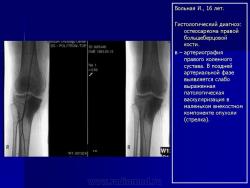

Для уточнения диагноза, локализации опухоли, выявления дополнительных очагов заболевания, определения ее отношения к окружающим тканям и контроля за эффективностью проводимой химиотерапии возможно проведение дополнительных исследований: компьютерная томография, магнито-резонансная томография, ангиография, остеосцинтиграфия, УЗИ.